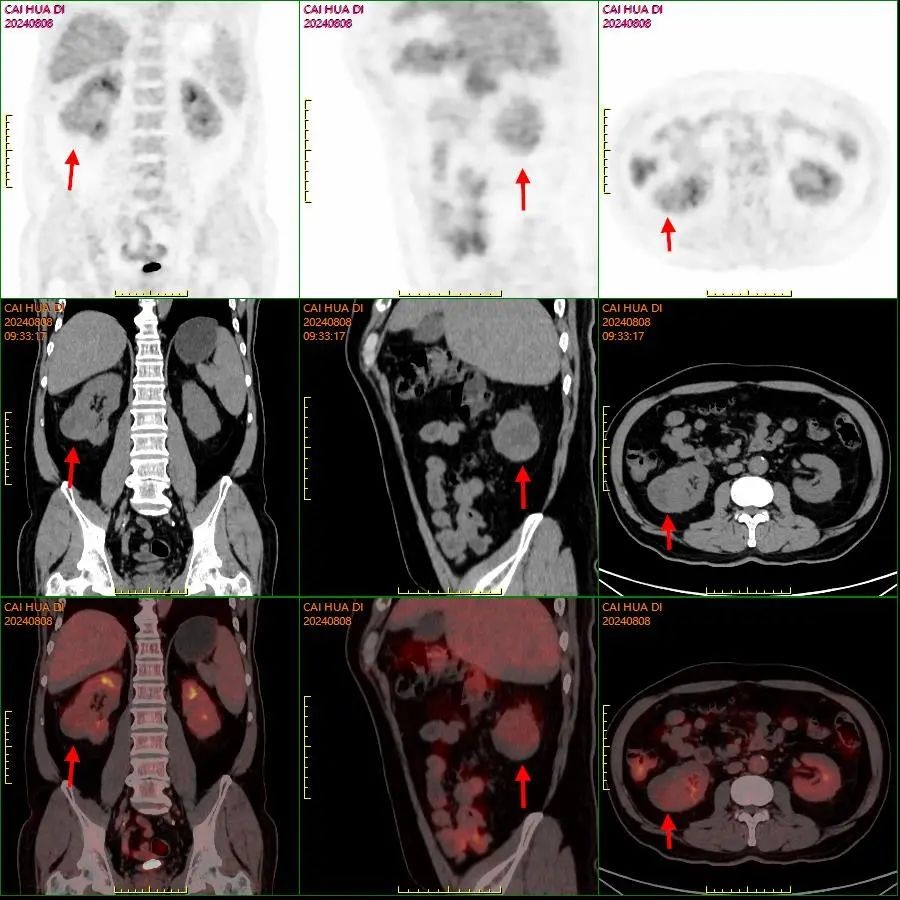

▲术前右肾癌PET-CT图像

经过阅片以及共同讨论,专家组认为,两处癌变均为原发性恶性肿瘤可能性大,在治疗先后的选择上,考虑到单侧肾所提供的肾功能不会影响后续的肺部手术,且左下肺囊性病变生物学行为较惰、囊腔型肺癌可能性高,可以先对右肾的癌变组织进行切除再针对左下肺癌变组织进行治疗;治疗期间实施全程的多学科协作管理,以确保前后两术的正常开展。

“囊腔型肺癌是一种以薄壁囊腔为主要表现或肺癌实性病灶继发囊腔的特殊类型肺恶性肿瘤,其发病率低,占肺癌的1~4%,约三分之二的患者有吸烟史”,张升解释,这种恶性肿瘤影像学与肺结核空洞及慢性肺脓肿等病变有相似之处,所以临床上常被误诊或漏诊,甚至因此延误治疗。